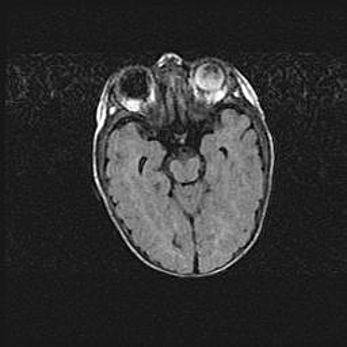

Церебральная ишемия II.

Возраст: 5 дней

Вес: 3400 г

Пол: женский

Окружность головы: 35 см

Срок гестации: 39 недель

Церебральная ишемия – это заболевание, характеризующееся недостаточностью (гипоксией) либо полным прекращением (аноксией) снабжения мозга кислородом по причине закупорки одного или нескольких сосудов. Это приводит к  что метаболическим расстройствам различной степени тяжести в тканях головного мозга, развитию коагуляционных некрозов и гибели нейронов.